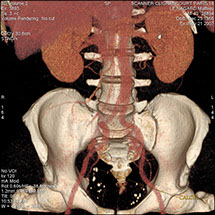

Le scanner comporte un lit d'examen, sur lequel le patient est allongé, qui va se déplacer lentement pendant l’examen et un anneau qui va tourner autour du patient en émettant des rayons X (il contient le tube à rayons X et les récepteurs). Les rayons X vont traverser la région à étudier et permettre d’obtenir des images en coupe de la zone à étudier. Des traitements de numérisation informatique permettront d'obtenir  des images 2D ou 3D dans différents plans et volumes.

On peut faire ressortir le contraste de certains tissus, en particulier des vaisseaux sanguins, en injectant un produit dit "de contraste" (contenant de l'iode) qui a la propriété de fortement absorber les rayons X et donc de rendre très visibles les tissus où ce produit est présent (qui apparaissent alors hyperdenses, c'est à dire plus "blancs" sur l'image).

Grâce aux scanners multidétecteurs (ou multi-barrettes) à acquisition spiralée, on obtient une exploration très précise d'un large volume du corps humain pour un temps d'acquisition de quelques dizaines de secondes.

• Les pathologies vasculaires (dilatations d’artères : anévrysmes, les rétrécissements : sténoses).